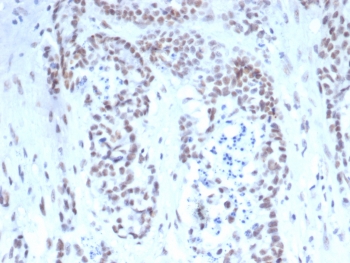

TARDBP Antibody Mouse Monoclonal Prostate IHC. Immunohistochemistry of TARDBP antibody in human prostate tissue. FFPE human prostate demonstrates predominantly nuclear HRP-DAB brown staining within glandular epithelial cells, consistent with the known nuclear localization of TAR DNA binding protein 43 / TDP-43 as an RNA-binding transcriptional regulator. Clone TARDP/349 was used as a mouse monoclonal antibody for detection. Heat-induced epitope retrieval was performed by boiling tissue sections in pH 9, 10 mM Tris with 1 mM EDTA for 20 minutes followed by cooling prior to staining.